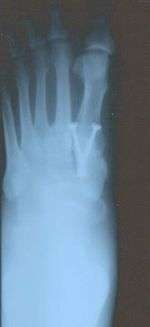

- Second metatarsal stress fracture (Fig. 5)

- Over-correction (Fig. 6)